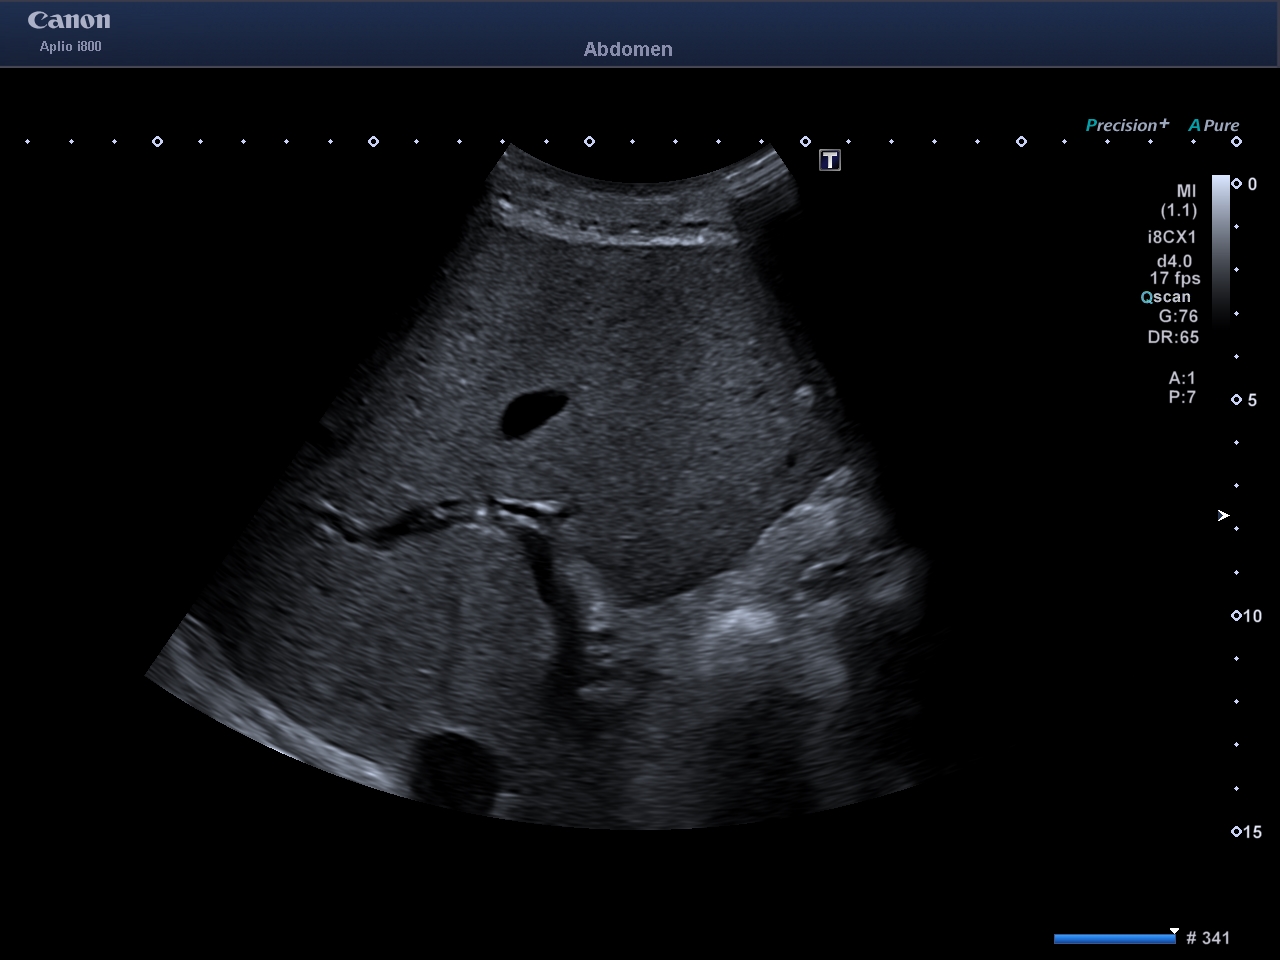

Ecografía abdominal: Con esta técnica podemos evaluar diferentes órganos intraabdominales: hígado, bazo, vesícula biliar, páncreas, riñones, vejiga y grandes vasos abdominales. Desde hace varios años disponemos de contrastes ecográficos intravenosos que nos ayudan a mejorar la caracterización de ciertas lesiones a nivel hepático, vía biliar, vasculares, entre otras. Su seguridad, ausencia de hepato o nefrotoxicidad nos permiten administrarlos en algunos pacientes con ciertas patologías, que de otra forma no podrían recibir otro tipo de contrastes.

Ecografía intestinal: con la obtención ecógrafos de nueva generación y de sondas de alta frecuencia, podemos evaluar el tubo digestivo, por lo que estamos usando esta ventaja para el diagnóstico, evaluación y seguimiento de pacientes con enfermedad inflamatoria intestinal.